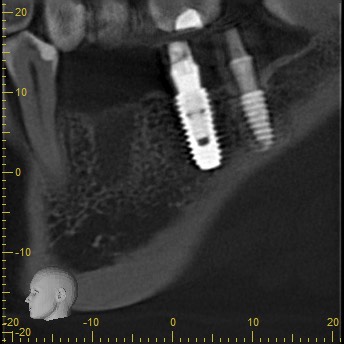

Імплантація